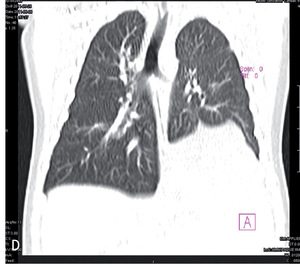

W piśmiennictwie medycznym większość publikacji na temat sekwestracji to zestawienia kilku do kilkunastu przypadków albo przeglądy piśmiennictwa.1,2,4,5 Największa przedstawiona grupa liczy 2625 chorych (zarówno dzieci, jak i dorosłych) i pochodzi z retrospektywnej analizy bazy danych, rejestrującej dobrze udokumentowane przypadki opisane w chińskim piśmiennictwie w latach 1998-2008.6 W tym materiale sekwestracje wewnątrzpłatowe stanowiły 84%, a zewnątrzpłatowe 16%. W obrazie radiologicznym sekwestracja przedstawiała się jako zmiany guzowate (46%), torbielowate (37%), jamiste (6%) lub naśladujące zmiany zapalne (10%). W obrazie tomografii komputerowej wysokiej rozdzielczości (HRCT) tych samych chorych uzyskano obraz zmian guzowatych (49%), torbielowatych (29%), jamistych (12%) lub naśladujących zmiany zapalne (8%) albo rozstrzeniowe (2%). U pojedynczych chorych zmiany miały obraz otorbionego wysięku.

Najczęstszą lokalizacją były płaty dolne: lewy (71,5%) bądź prawy (26%), rzadko lewy górny (2%), a wyjątkowo pozostałe. W płatach dolnych najczęściej zajęty był segment podstawny tylny (88%). Tylko u 3 chorych (0,1%) stwierdzono zmiany obustronne.

Rozwój technik obrazowania umożliwia wykrycie wielu wad rozwojowych w życiu płodowym. Sekwestracja zewnątrzpłatowa może być uwidoczniona od 16 tygodnia życia płodowego. Widoczna jest w postaci ogniska hiperechogenicznego i stanowi około 16% ujawnianych w okresie przedurodzeniowym zmian płucnych. Wymaga różnicowania z gruczolakowatością torbielowatą płodu (cystic adenomatoid malformation), wrodzoną rozedmą miąższu płucnego, wadami serca, wrodzoną przepukliną przeponową, przetoką tchawiczo-przełykową, torbielami oskrzelopochodnymi czy zmianami rozrostowymi, takimi jak np. neuroblastoma umiejscowiona w śródpiersiu.1,7 Diagnostykę różnicową ułatwia zastosowanie ultrasonografii doplerowskiej8 i/lub rezonansu magnetycznego.9